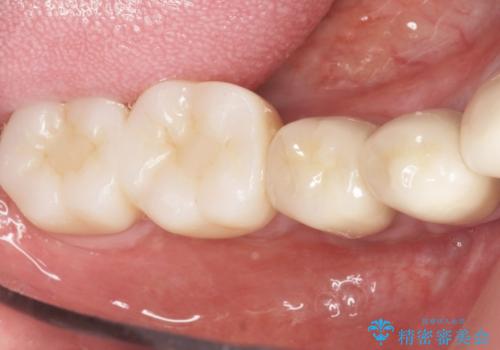

再生療法と骨外科処置により、歯周ポケットは全周2mm以下に改善されました。

保存が難しいと思われた歯を残すことができ、患者様にご満足頂けました。

歯周病治療と連結補綴により歯の動揺がなくなり、「なんでも食べられます!」と喜んで下さいました。

クラウンの種類:メタルボンドクラウン エコノミー